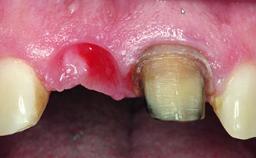

Replacement of a Missing Upper Left Central Incisor: Late Placement of an RC Bone Level Implant, CAD/CAM Zirconia Abutment

A healthy 37-year-old female patient was referred for a consultation on the replacement of missing tooth 21 with an implant-supported restoration. She stated that several years previously the tooth had been traumatically avulsed following a motor vehicle accident. The tooth was replaced with a three-unit fixed partial denture (FPD) immediately afterwards. Over time, she became disillusioned with the FPD and looked for a different option, including orthodontic therapy. She presented still in her orthodontic appliances, with the pontic sectioned free from the FPD but attached to the archwire. Her orthodontist felt that orthodontic treatment had been successfully completed, but nevertheless referred her before removing the appliances in case adjustments were necessary.

Bone Volume Deficient horizontally, allowing simultaneous augumentation